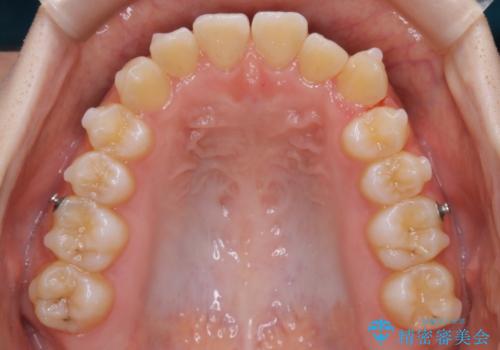

【非抜歯】すきっ歯と噛み合わせの治療

- 上の前歯のすきっ歯と下の前歯のガタつきを主訴にご来院されました。

噛み合わせの改善も同時に進めつつ、主訴の部分も効率的に治していくためマウスピース装置でゴムかけを行いながら治療を進めていきました。

正中離開(すきっ歯)

真ん中の歯が左右に開いてしまい隙間ができてしまう状態を「正中離開」といい、俗にすきっ歯と呼ばれています。

隙間を埋めていく方向に歯を移動させることで改善していくケースが多く、比較的治りやすい不正咬合のひとつとされています。

しかしながら、歯が捻じれていたり、噛み合う歯との位置関係によっては治療が難しくなる場合があります。